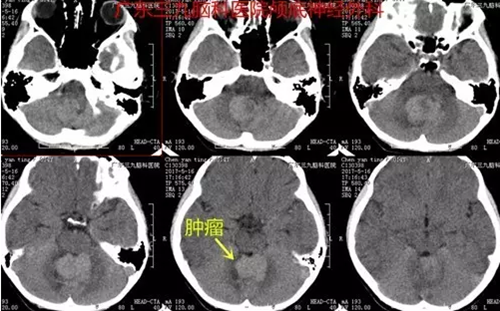

图1:术前CT提示四脑室-小脑蚓部一团块状稍高密度占位性病变

据家属介绍,起初以为芳芳因学习压力大导致头痛,所以并未太过在意。可芳芳头痛3天后,出现了呕吐症状。家属遂带她到医院检查CT,发现她的四脑室-小脑蚓部有一团块状稍高密度占位性病变。今年5月,芳芳一家人来到广东三九脑科医院。